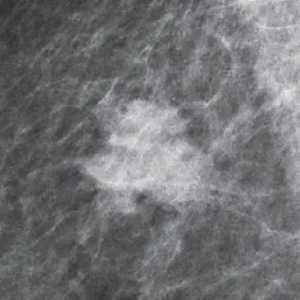

乳腺X线检查是用两个压迫板夹住乳房,然后用X光进行拍照,通过比对正常乳腺组织和病变组织来判断病灶的性质。

在X线下,我们能清楚地看见乳房内组织与病变。

● 肿块:大小、形状、边缘和密度4个方面观察肿块。

● 钙化:可分为典型的良性钙化和可疑钙化。

● 结构扭曲:正常结构被扭曲但无明确的肿块可见,包括从一点发出的放射状影和局灶性收缩,或在实质的边缘扭曲。